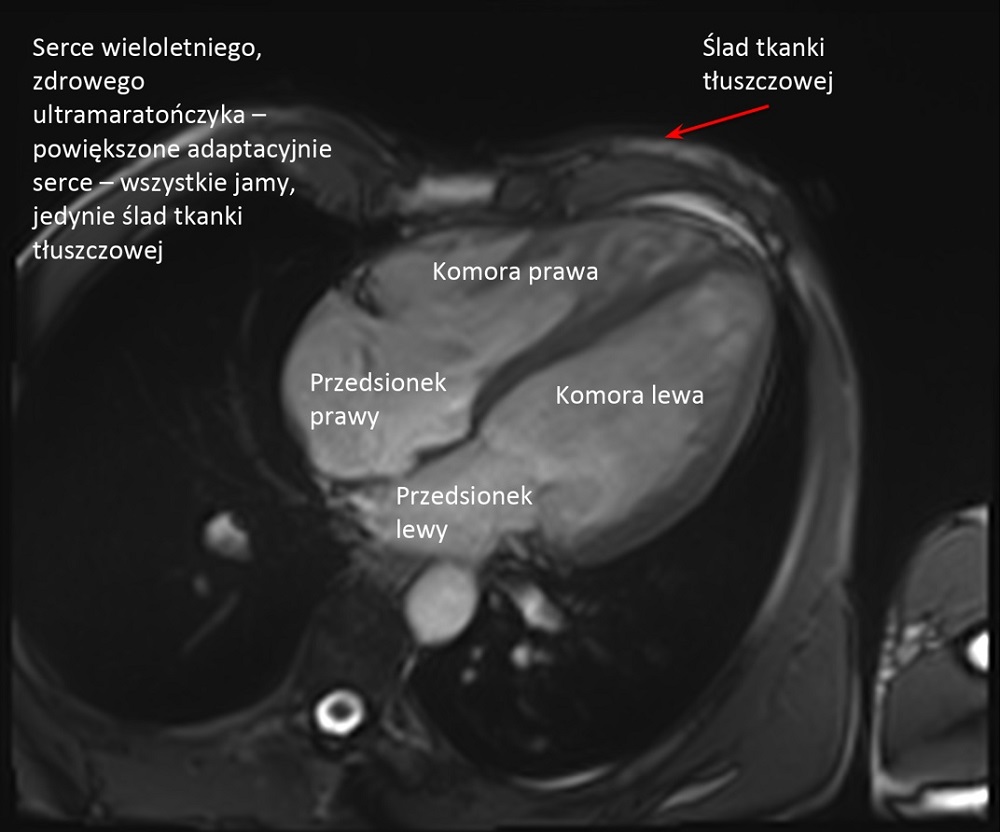

– Organizm osoby biegającej długo i duże objętości, trenującej wiele godzin tygodniowo, podlega tak zwanym zmianom adaptacyjnym. Jestem kardiologiem, więc powiem jak to wygląda patrząc od strony serca: zwalnia się rytm, serce jest bardziej spokojne, powiększają się jamy serca.

Obu komór i obu przedsionków. One wszystkie powiększają się symetrycznie. Grubieje także trochę mięsień, natomiast raczej nie poszerza się aorta. Kurczliwość mięśnia sercowego w spoczynku może być na granicy dolnej normy, bo ono wtedy odpoczywa, natomiast w wysiłku radzi sobie i reaguje znakomicie.

W porównaniu do grupy kontrolnej, czyli mężczyzn w tym samym wieku nie uprawiających sportu, nie stwierdziliśmy żadnych cech uszkodzenia mięśnia sercowego czy anomalii w funkcjonowaniu układu krążenia, za to większość parametrów była znacznie korzystniejsza: cholesterol był niższy, tkanka tłuszczowa mniejsza, lepsze ciśnienie krwi. To wszystko pokazuje, że ultra jest korzystne dla zdrowia serca.